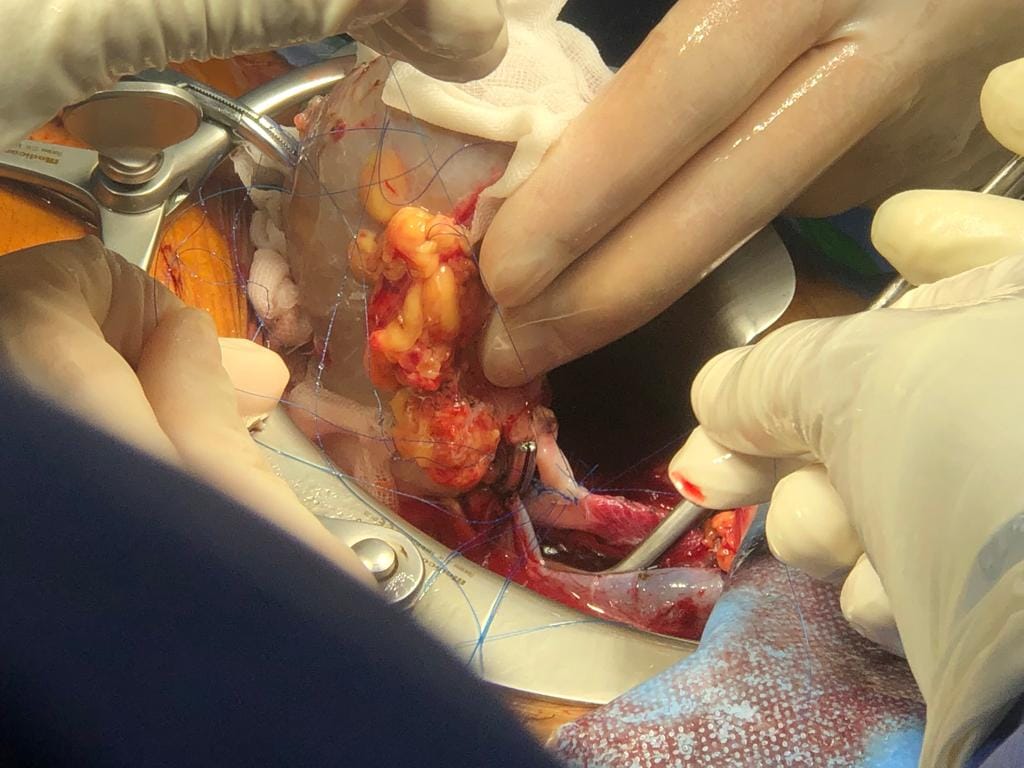

وكشف الدكتور هشام مختار حمودة مدير وحدة زراعة الكلى أن الحالة رقم 48 كانت زراعة كلى لشاب يبلغ من العمر 23 عام وبتبرع من والده الذى يبلغ من العمر 45 عام، والتى كانت عملية حرجة ومعقدة لوجود جلطة متكلسة بأوردة الطرف السفلى الأيمن ممتدة إلى الوريد الاجوف السفلى حتى مستوى قريب من الكليتين الأصليتين وهى ما تعتبر أحدى الحالات النادرة جداً وتمثل تحدياً للفريق الطبي الجراحي .

مضيفاً أن الحالة رقم ٤٩ تمت لشاب عمره ٢٣ سنة أيضا وكانت المتبرعة أخت المريض ذات ٢٢ عاما وكانت هذه الحالة تحدياً خاصاً حيث كان المريض لديه نسبة أجسام مضادة اعلي من المعتاد قبل العملية وهو ما يجعله أكثر عرضة لرفض الكلية المزروعة مما يمثل صعوبة تهدد نجاح الجراحة مما استدعى إعطاء ادوية مثبطة للمناعة خاصة وقوية قبل وأثناء وبعد العملية وتم وبفضل الله التعامل مع الحالة بمهنية وسياسة علمية صحيحة وبإرادة قوية من الفريق للنجاح وحرصهم على توفير الرعاية الصحية السليمة لهذا المريض.

وكشف الدكتور هشام حمودة عن خروج المرضى من المستشفى بوظائف كلى طبيعية ، متوجهاً بشكره إلى كافة أعضاء الفريق الطبي من أساتذة وأطباء متخصصين فى مجالات جراحة المسالك البولية والتخدير والباطنة وبتعاون أطباء الأشعة والباثولوجيا الإكلينيكية والصيدلة الإكلينيكية وفريق التمريض .